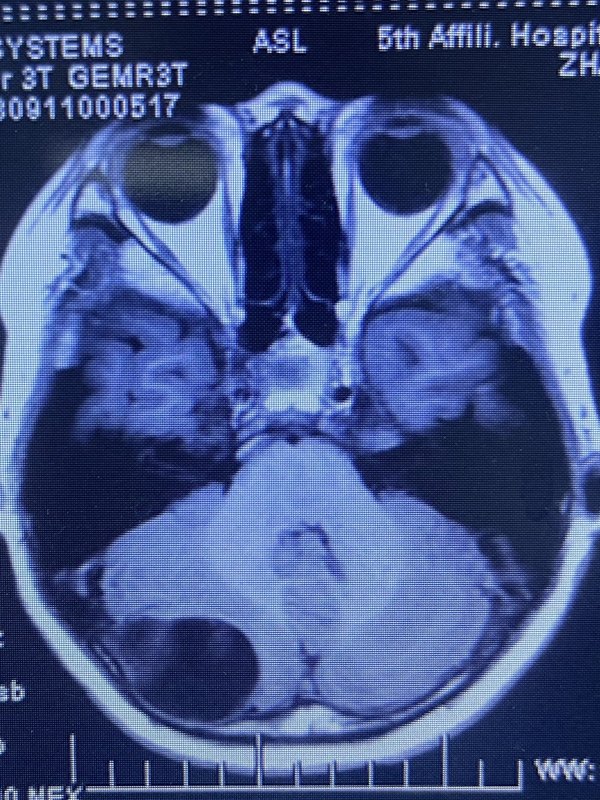

中后顱窩巨大腫瘤